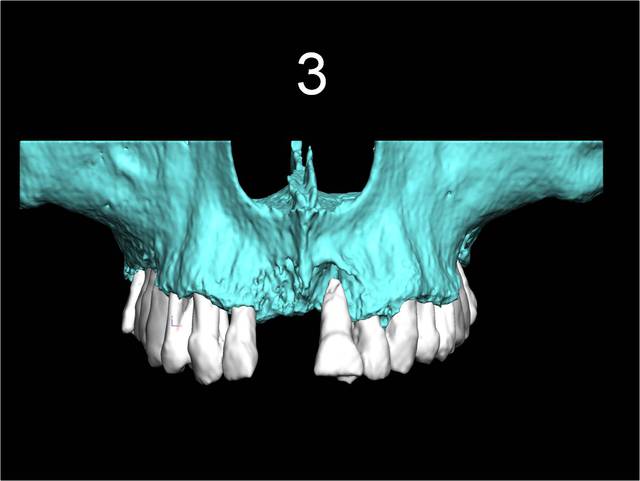

3

Celui la est très moyen au niveau osseux

22 implants au total et pas une seule vis!

Pluton 2 max stab, tu vois cela m'arrive aussi d'en mettre!